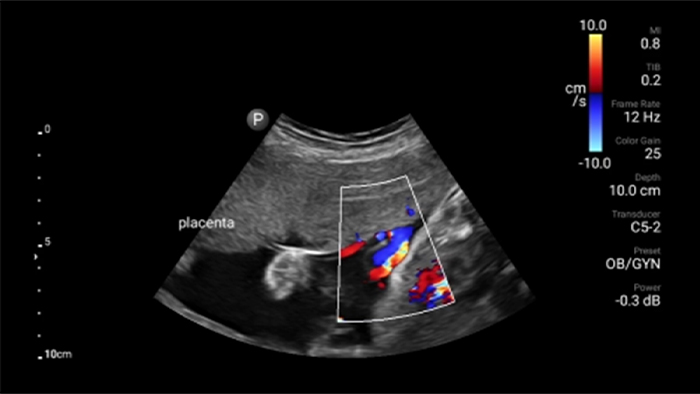

Lumify C5-2 broadband curved array transducer

• 5 to 2 MHz extended operating frequency range • 50mm radius of curvature • 2D, color Doppler, M-mode, advanced XRES and multivariate harmonic imaging, SonoCT • High-resolution imaging for deeper applications: abdominal, gall bladder, OB/GYN and lung imaging preset optimizations • Center line marker • USB-C transducer with replaceable cable